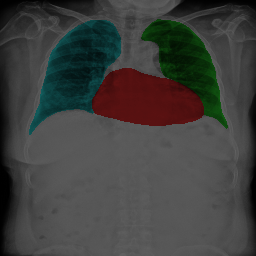

The task of chest organ segmentation is a simple benchmark task in medical image segmentation. In this task, we consider three semantic classes, namely left lung, right lung, and heart. We can easily control the environment to get an insight into the impact of the limited partial labels on various representative partially supervised methods and the efficiency of VLUU. Without specification, the experimental comparison is conducted in such a way that different models use the same network backbone, loss function, training strategy, and the set of hyperparameters.

We use three partially labeled datasets as the training set and one fully labeled as the test set, where the four datasets are collected from four different sources. We choose this setup to simulate the practical scenarios where dataset shift exists, which is a challenging situation for DL models. We use the JSRT dataset as the left lung dataset, denoted as L. We use a subset of the Wingspan dataset containing 18 CXRs as the right lung dataset, denoted as R. We use another subset of the Wingspan dataset containing 18 CXRs as the right lung dataset, denoted as H. We use the rest of the Wingspan dataset as the fully labeled test set, which contains 185 CXRs, and denote it as T. The visual comparison of the data modalities of the four sets can be viewed in Fig. 5. Note, all four sets are collected from 4 different sources (hospitals with different imaging protocols).